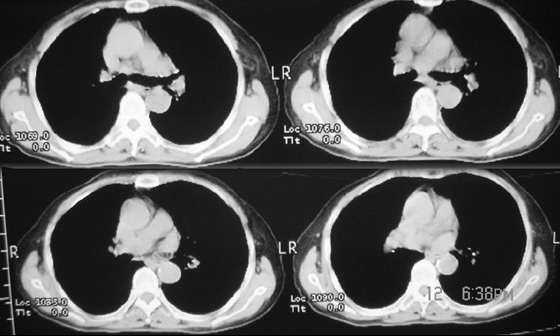

女,80岁。因咳嗽,声音嘶哑1月

不是我想做强化,我对体部病灶一直是强调要强化的,可皮试第5分钟患者有头痛,加上高龄,为了减少医疗纠纷就只好不做。望战友理解。此病灶我觉得首先要明确是来1,自于肺内还是纵隔内?2,在扫描层内见右肝与隔之间内见囊壮均匀水样低密度区,于肝关系密切,首先考虑是肝囊肿{由于没有强化故不好说,只有建议患者行进一步检查!}

郁闷!病灶和主动脉弓是宽基底相连,但主动脉弓壁是清晰可见;肺窗示病灶边缘见不规则毛刺样改变;肝左叶见巨大囊性病灶。我考虑胸部病灶是纵隔型肺癌,肝内病灶不好说是啥。

假型动脉瘤 1 其和动脉开口小时主动脉弓壁是清晰可见 2此病人上叶前段有病变所以病灶边缘见不规则毛刺样

影象表现:左上肺纵隔旁可见一形态略不规整的软组织肿块(上自主动脉旁,下至左肺动脉上层面);

密度较均匀;最大层面与主动脉弓呈宽基底,但与其可见一线状低密度影分割,下方与尖后段

支气管内侧壁和左上肺静脉分界不清(尖后段支气管未见明显狭窄)双肺血管纹理明显增多

以右侧明显并可见胸膜下线 不规则线状影和中叶的斑片状影;左膈明显升高。

临床表现:老年女,80岁。以咳嗽,声音嘶哑1月为主诉。

影象诊断:考虑纵隔型肺癌伴纵隔淋巴结转移.肺内炎变待除外.肺内转移建议hrct

病灶和主动脉弓是宽基底相连,但与主动脉弓壁之间的脂肪间隙清晰可见;肺窗示病灶边缘有不规则毛刺样;左肺叶段肺气肿;左侧横膈升高。右肺中叶炎变;结合病史考虑纵隔型肺癌可能性大。其他的难说!

左上肺纵隔旁可见一形态略不规整的软组织肿块,与主动脉弓壁之间的脂肪间隙清晰,肺窗示病灶边缘有不规则毛刺样改变,右肺中叶炎症。综合病史考虑纵隔型肺癌。

部分见肝内大圆形低密度灶影,包膜完整,考虑肝囊肿。